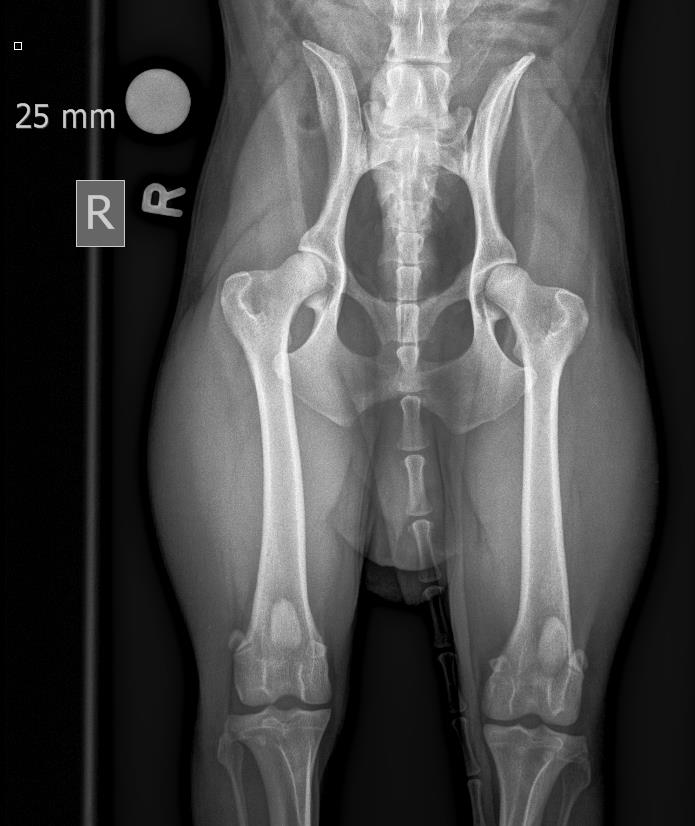

• HD Abklärungen

HD und ED Beurteilungen werden nach Wunsch des Besitzers oder nach Vorgaben der Rasseklubs jeweils von der HD-Kommission in Zürich oder Bern beurteilt. Für unsere deutschen Kunden ist auch ein Versand nach Deutschland möglich